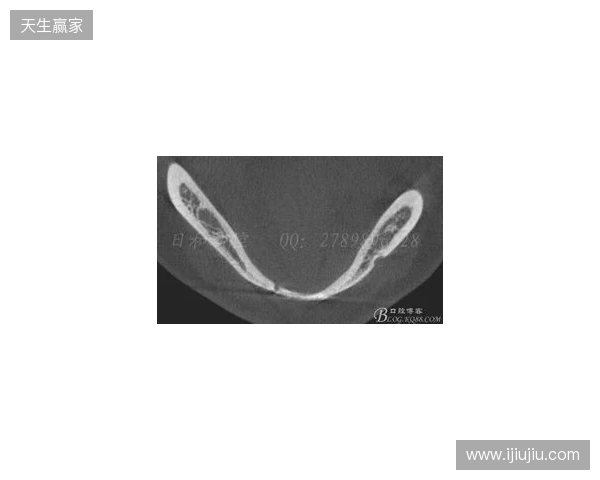

在2026赛季中超联赛首轮的比赛中,韦林顿·席尔瓦遭遇了严重的伤病,导致他上唇部受伤,并且出现了牙齿和牙槽骨的损伤。根据华西口腔医院的诊断,席尔瓦的伤情包括上唇部贯通伤、两颗牙齿半脱位以及上颌前牙区牙槽骨骨折。此事件不仅对球员本人构成了巨大的身体挑战,也给球队带来了不小的影响。伤病的发生让人揪心,球迷们纷纷为席尔瓦送上祝福,希望他能尽快康复,重返赛场。

根据医院的检查结果,韦林顿·席尔瓦的上唇部受伤程度较为严重,属于贯通伤,已经进行了清创缝合。这种类型的伤势不仅影响外观,还可能对球员的饮食和发声造成影响。更为严重的是,他的上颌前牙区还出现了骨折,意味着席尔瓦在恢复期间将面临长时间的治疗和康复过程。

球员的第11和第21牙出现了半脱位的情况,这可能会导致他在恢复后需要进行进一步的牙科治疗,甚至有可能影响到他今后的职业生涯。医生表示,虽然通过手术和治疗可以恢复,但心理层面的恢复同样重要。